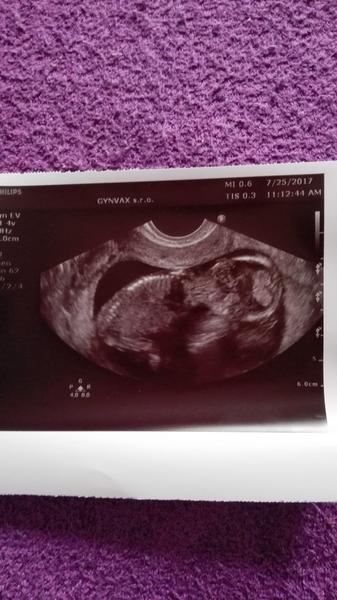

@kaki221 gratulujeem 🙂 a drzim palce nech aj nadalej ide vsetko ako po masle 🤰

@kaki221 Gratulujem. Drobčiatko je krásne. Držím palce, nech to naďalej pokračuje čo najlepšie... ❤🤰👶